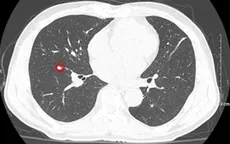

VTV.vn - Khám tại Bệnh viện Bạch Mai, bệnh nhân được chẩn đoán mắc ung thư phổi và ung thư đường mật.